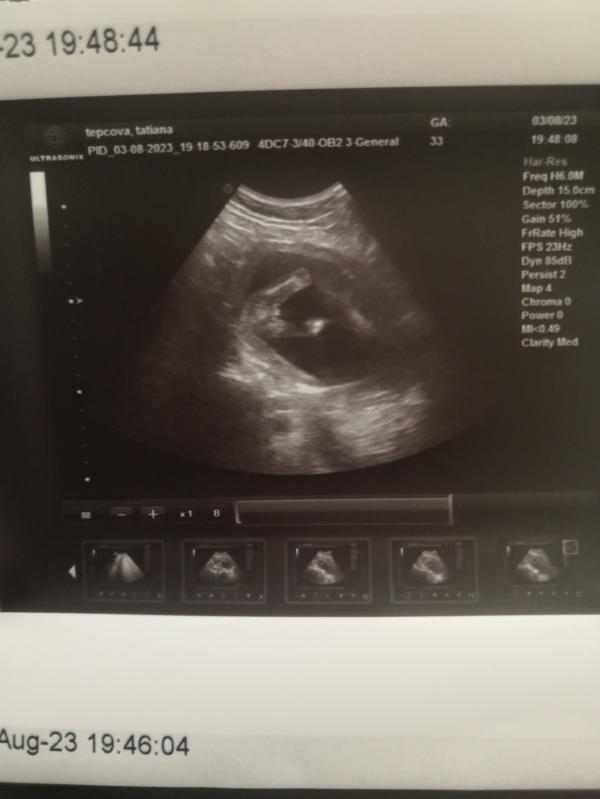

Мне кажется девочка, посередине разделение как будто, а врач не сказал вам пол? Предположительно

Она сказала что "ей кажется, что мальчик". Оттого я и дала возможность пованговать мамлайфу)

Я впервые понимаю, что изображено на узи. Это же ножки и попка, да? А что между ножками тут все гадают?)

Да, верно, "вид снизу"))

А мне кажется, что девочка, как будто складочка между есть 🙈

Мне кажется девочка, у моего явно хозяйство просматривалось на вашем сроке)